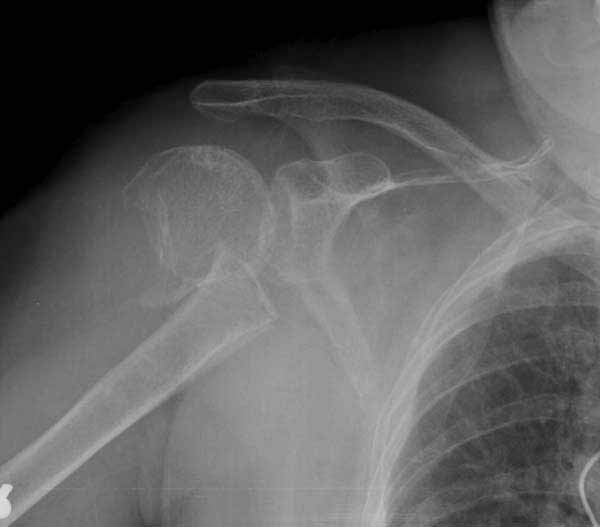

Уважаемы коллеги! Прошу помочь определиться с тактикой лечения пациентки. В феврале в отделение поступила пациентка с оскольчатым переломо-вывихом головки плечевой кости. Выполнена операция -остеосинтез блокируемой пластиной. Костная пластика не производилась. На контрольных рентгенограммах остается сублюксация головки и смещение большого бугорка. Интраоперационно бугорок подшивался с помощью лавсановых нитей. Послеоперационно: ношение косыночной повязки и пассивные движения в плечевом суставе в течение 2,5-х месяцев без особенностей. Через 2,5 месяца при попытке выполнения пассивно-активных движений произошел передний вывих плечевой кости.Вся реабилитация производилась по месту жительства. Таким образом существование вывиха в течение 1 месяца. Боли не беспокоят. Нейрососудистых нарушений в конечности нет. Что вы можете посоветовать: пластику, эндопротез, артродез? Заранее спасибо.

мне кажется ,что на послеоперационном снимке, также имеется сублюксация головки.сколько годов пациентке?

Уважаемый коллега. На мой взгляд имеющаяся дислокация головки обусловлена на мой взгляд имеющейся у пациента обширной травмой ротаторного аппарата. В пользу данной точки зрения могу привести следующее: на представленных Вами рентгенограммах хорошо заметен отрыв большого бугорка со смещением отломков который как известно является точкой прикрепления коротких наружных ротаторов плеча. Последующая миграция данного фрагмента и неполноценная репозиция его при первичном остеосинтезе с нестабильной фиксацией на мой взгляд и обусловили создавшуюся ситуацию. то что пациента не беспокоят боли позволю подвергнуть сомнению поскольку сам занимаюсь хирургией плеча и с подобными ситуациями сталкивался неоднократно. На мой взгляд в настоящее время целесообразно проведение повторного оперативного вмешательства с адекватным восстановлением ротаторного аппарата, поскольку дальнейшее затягивание сложившейся ситуации уменьшает шанс на успех данного вмешательства.

Набор мелких снимков не отражает истинную картину суставной поверхности лопатки, а также качество репозиции головки плеча. Необходимо доказать аксиальным снимком наличие покрытия головки. Правильная маркировка на рентген снимках и соответствие с выставленным диагнозом гарантирует от ошибок со стороной во время операции!

Для адекватного лечения необходимо знать состояние костного компонента - нужно КТ с артрографией что поможет частично оценить состояние сухожилий и лабриум. Уже по снимку можно сказать что существует большой костный дефект в задне-наружном сегменте.